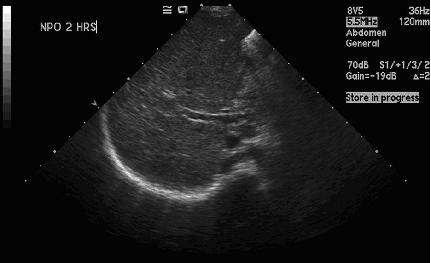

La colestasi � presente nella quasi totalit� dei pazienti; si manifesta solitamente nei prima 2 anni di vita con la comparsa di ittero, epatosplenomegalia, feci acoliche, urine ipercromiche e malassorbimento, associati ad un aumento degli indici di colestasi (bilirubina diretta, sali biliari, transaminasi, γ-GT, fosfatasi alcalina) e iperlipidemia (colesterolo totale e trigliceridi). La met� dei casi evolve in ipertensione portale7. A tutto ci�, nell�80% dei casi, si associa scarsa crescita legata ad un bilancio energetico negativo secondario ad incremento del consumo energetico, ridotto introito calorico e malassorbimento lipidico; i bambini con sindrome di Alalgille, infatti, presentano il difetto di crescita pi� severo tra tutte le forme di colestasi12. La diagnosi, oltre che clinica e laboratoristica, utilizza tecniche di imaging (ultrasonografia, colangiografia, colescintigrafia, colangio-RMN), le quali rilevano l�atresia biliare con riduzione della secrezione nel tratto gastrointestinale (figura 2 e Figura 3). La conferma diagnostica � data dalla biopsia epatica e dalla ricerca delle mutazioni genetiche7.

Figura 2. Ecografia epatica dopo 2 ore di digiuno: assente dilatazione vie biliari intraepatiche e mancata evidenziazione di dotto biliare comune e colecisti